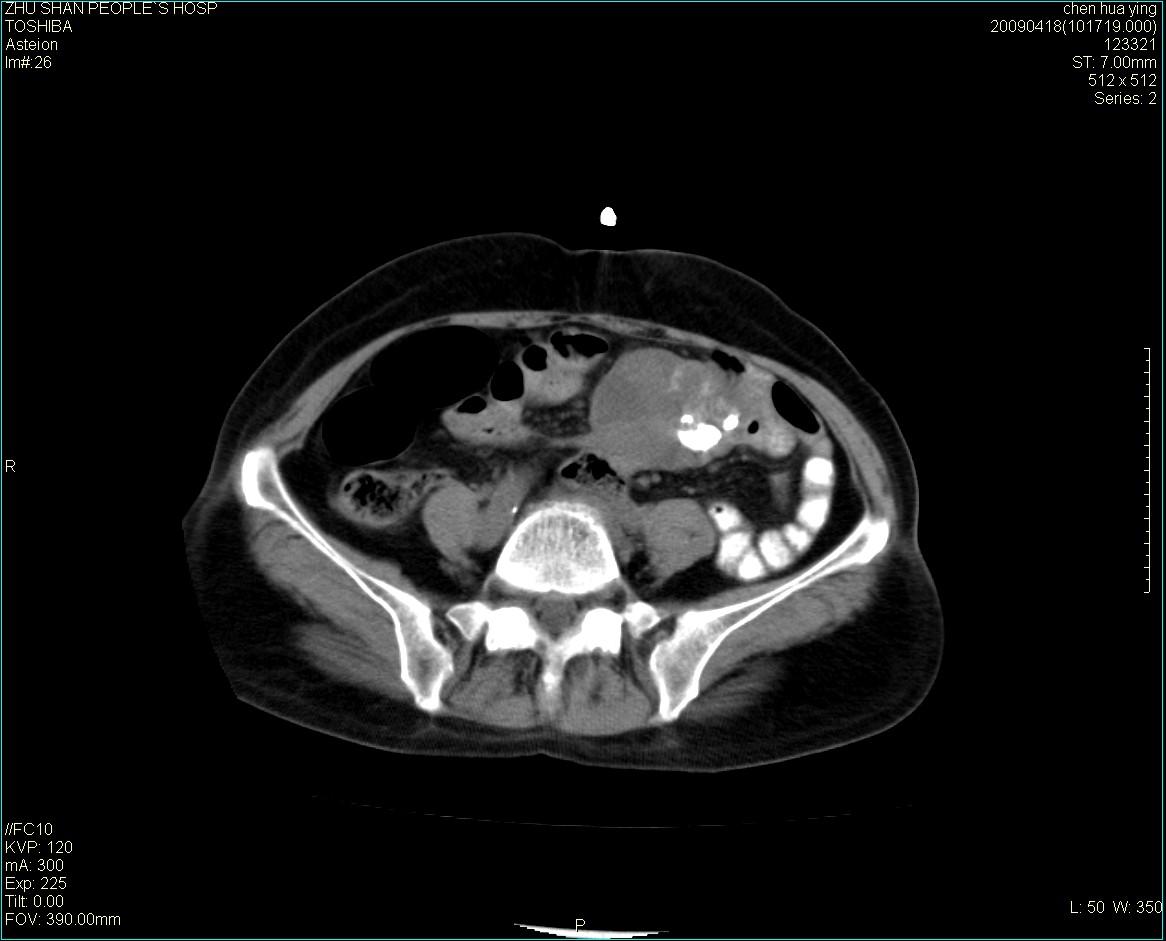

女性病人 65岁 腹部包块半年余结肠造影未见异常.

病灶略呈圆形有分叶状,上部层面呈实性,右侧见圆形低密度区,灶内见团块状钙化,病灶下方与肠管分境不清,考虑间质瘤可能性大,建议肠道准备后增强